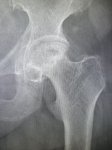

IMG20251009125406.jpg

Где пиздецома?

>>325599559

Типичный рак легких

вообще, как клинический диагноз. я бы предположил тубик, тут и затемнения есть и в корнях кругленькие л/у? и какая то диссеминация справа.

Сегментарная пневмония?

>>325604664

нит